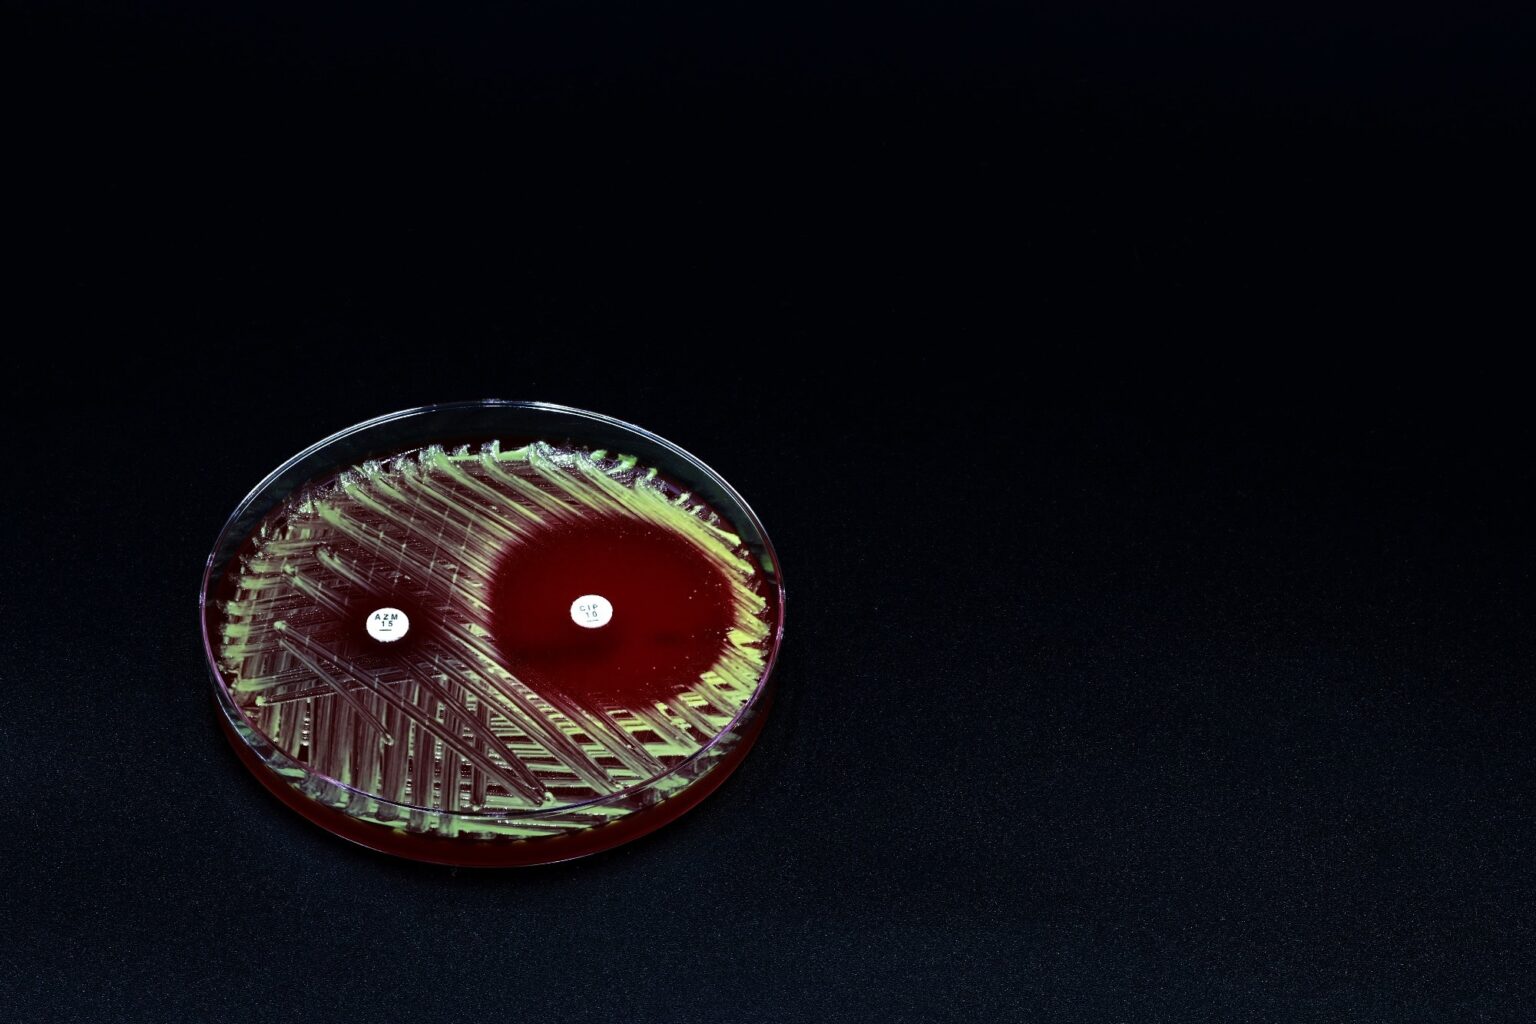

Study: Heteromultivalent Nanogels as Highly Potent Inhibitors of Pseudomonas Aeruginosa. Image Credit: TopMicrobialStock/Shutterstock.com

Study: Heteromultivalent Nanogels as Highly Potent Inhibitors of Pseudomonas Aeruginosa. Image Credit: TopMicrobialStock/Shutterstock.com

P. aeruginosa is a leading cause of hospital-acquired infections, especially in immunocompromised patients. Its ability to form biofilms enables it to evade antibiotics and immune responses.